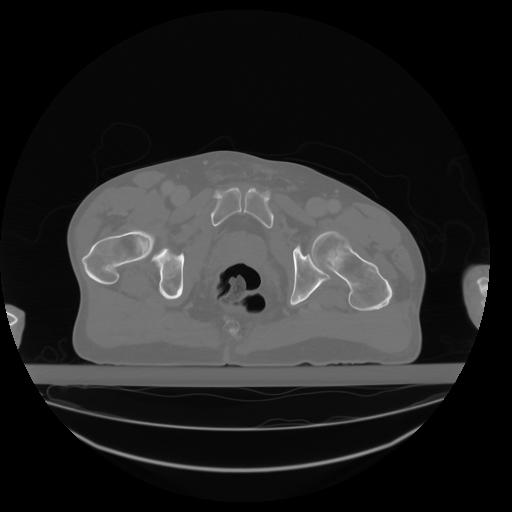

27 CUERPO,CE,Axial,3.0,CUERPO,,